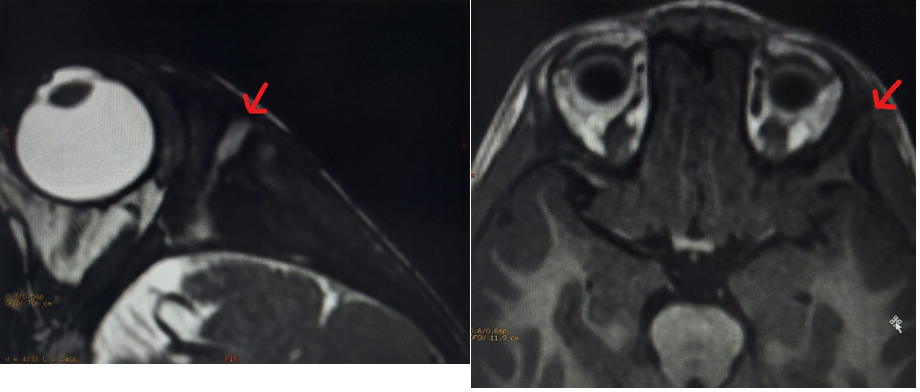

A 29-month-old boy presented to the emergency department with a 48-hour history of left palpebral swelling without inflammatory signs or other associated symptoms. No precipitating factors were identified. The parents reported three previous similar episodes in the last 1.5 years with spontaneous resolution within 48-72 hours. The other episodes were associated with serous drainage. On examination (Figure 1) there was a left palpebral soft swelling with extension to the frontal region. In the middle of the tumefaction there was a one-millimeter orifice, without spontaneous or by expression drainage. A soft tissues ultrasound was performed at the Emergency Department, that revealed a fistulous path from clinically evident dermal lesion with apparently intracranial extension, without signs of local complications. A magnetic resonance imaging (MRI) corroborated the ultrasound findings (Figure 2). In the present case, the patient was discharged with a programed neurosurgery appointment. The boy has maintained regular follow-up in pediatric and neurosurgery consultations, waiting for spontaneous resolution, once there were no major complications in the two-year follow-up period.

Figure 1. Lateral view from the head swelling.

Figure 1. Lateral view from the head swelling